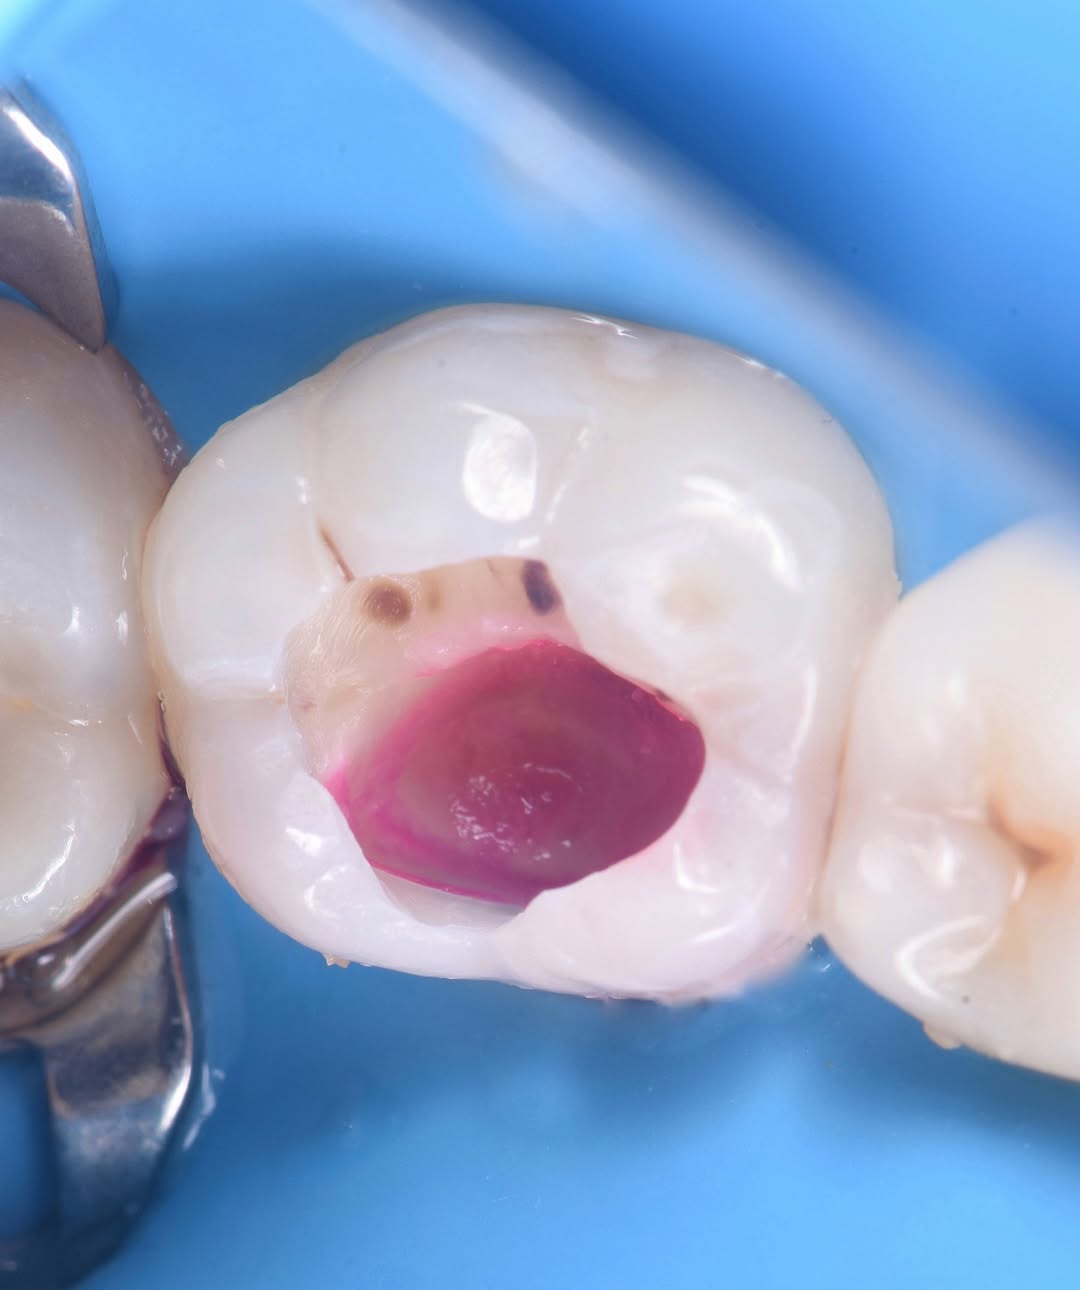

Проведена обработка кариозной полости с последующей эстетической реставрацией✔️ Красота - в здоровых зубах ???????????? #dentist #baku

???? Qaygi ile Daha bir dish xilas edildi ✨#dental #baku